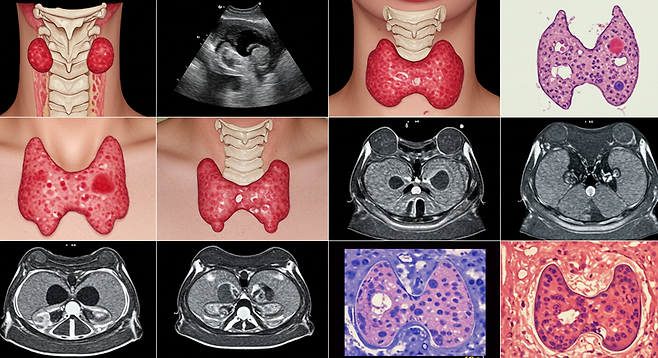

갑상선암은 우리나라에서 발생률이 높은 암 중 하나로, 특히 여성 암 발생률 1위를 차지하고 있습니다. 흔히 '착한 암' 또는 '거북이암'이라 불리며 진행 속도가 느리고 예후가 좋은 편이지만, 초기에 발견하지 못하면 다른 장기로 전이되어 생명을 위협할 수도 있습니다. 갑상선은 목 앞쪽에 위치한 나비 모양의 내분비 기관으로, 우리 몸의 대사 과정을 조절하는 중요한 역할을 합니다. 이 작은 기관에 생기는 암의 초기 신호를 알아두면 조기 발견과 치료에 큰 도움이 됩니다.

갑상선암은 초기에 발견하면 치료 성공률이 매우 높습니다. 초기 갑상선암의 5년 생존율은 90% 이상으로, 조기 발견과 적절한 치료가 중요합니다. 갑상선암 검진은 주로 목 초음파 검사와 갑상선 세침흡인 검사를 통해 이루어집니다.